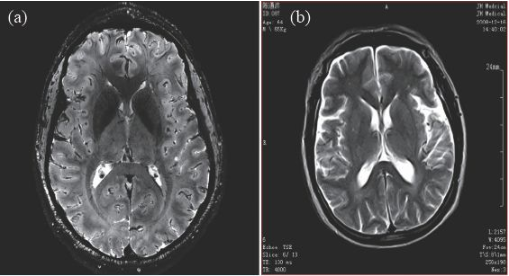

因此,磁共振成像技術(shù)目前的發(fā)展趨勢(shì),是朝著更高磁場(chǎng)強(qiáng)度發(fā)展,以期獲得更高分辨率的圖像,并實(shí)現(xiàn)多核成像。圖6 顯示了磁場(chǎng)強(qiáng)度的高低對(duì)圖像分辨率的影像,(a)為7 T 磁場(chǎng)下的圖像,(b)為0.35 T磁場(chǎng)下的圖像,二者的圖像分辨率可見一斑。

圖6 T2 加權(quán)成像(a)7 T 下的成像,分辨率約0.3 mm;(b)0.35 T下的成像,分辨率約1 mm